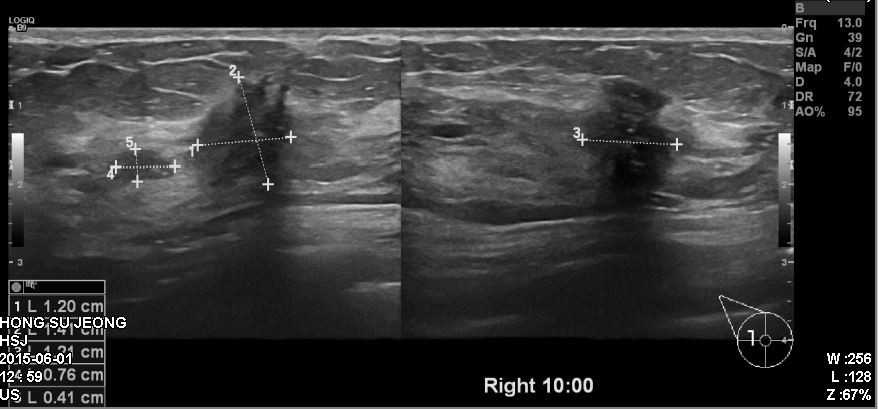

건강검진상 이상소견으로 내원하신 50대 여성 분으로 우측 10 :00 방향에서 5cm 떨어진

거리에 의심되는 혹 조직검사 시행하여 우측 침윤성 유관암 진단 되었습니다.